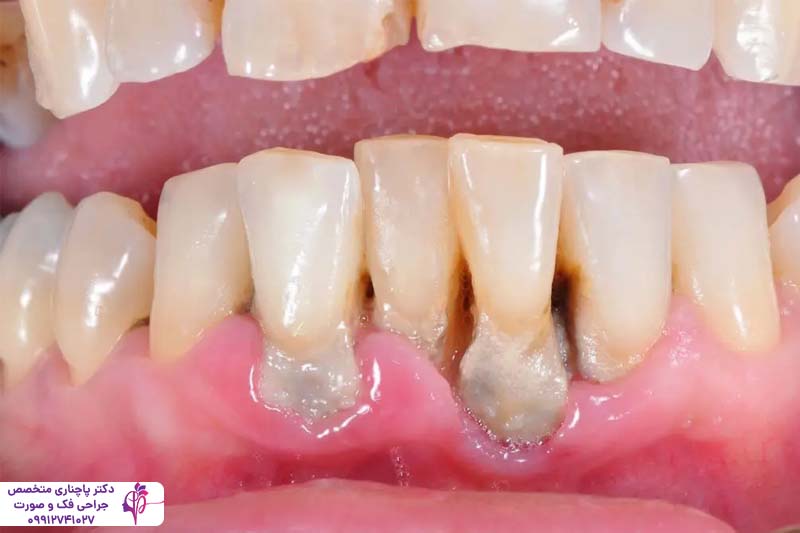

پریودنتیت مرحله پیشرفتهتر و جدیتر بیماری لثه است که در صورت عدم درمان ژنژیویت ایجاد میشود. در این مرحله، عفونت باکتریایی از سطح لثه به بافتهای عمیقتر، از جمله استخوان نفوذ میکند. باکتریها باعث ایجاد کیسههای عفونی یا کیسههای پریودنتال بین دندان و لثه میشوند و به تدریج به عمق بافت لثه نفوذ میکنند و باعث تجمع بیشتر پلاک و جرم میشوند. این مرحله از بیماری پریودنتال به تدریج باعث تخریب بافت لثه و استخوان میشود و در موارد حاد حتی با عقب راندن لثه باعث شل شدن دندانها و رد نهایت افتادن آنها میشود.

این مرحله از بیماری خودش را با خونریزی مداوم لثه، بوی بد دهان و حساسیت شدید دندانها به گرما و سرما و حتی درد در هنگام جویدن نشان میدهد. این مشکل در موارد شدید بافت لثه را کامل از بین میبرد و ریشه دندان نمایان میشود. بر خلاف ژنژیویت این مشکل نیاز به درمان حرفهای از طرف دندانپزشگ دارد. درمان بیماریهای لثه قبل از ایمپلنت در این مرحله شامل تمیز کردن عمیق توسط دندانپزشک، جراحی لثه یا حتی استفاده از آنتیبیوتیکهای قوی میشود. برای بیمارانی که قصد انجام ایمپلنت دارند درمان این مرحله از بیماری لثه قبل از ایمپلنت اهمیت زیادی دارد چون عفونت فعال باعث التهاب در اطراف ایمپلنت میشود و در نتیجه کاشت با شکست مواجه میشود.

تاثیر تحلیل رفتن استخوان فک روی دندانها

تحلیل رفتن استخوان فک یکی از عواقب جدی بیماریهای لثه است که مستقیما دندانها را تحت تاثیر قرار میدهد. وقتی عفونت به استخوان نفوذ میکند، بدن برای مبارزه استخوان را جذب میکند، که این منجر به کاهش حجم استخوان میشود. این تحلیل رفتن استخوان فک باعث شل شدن دندانها میشود چون بستر محکمی که ریشهها را نگه میداشت دیگر وجود ندارد. علاوه بر این تحلیل رفتن استخوان فک ظاهر صورت را تغییر میدهد، فک کوچکتر به نظر میرسد و گونهها فرو میروند. این موضوع برای کاشت ایمپلنت اهمیت زیادی دارد چون پایهها برای محکم شدن به یک بستر استخوانی قوی نیاز دارند. درمان بیماریهای لثه قبل از ایمپلنت جلوی این تحلیلرفتگی را میگیرد در موارد حاد هم پیوند استخوان میتواند این مشکل را برطرف کند.